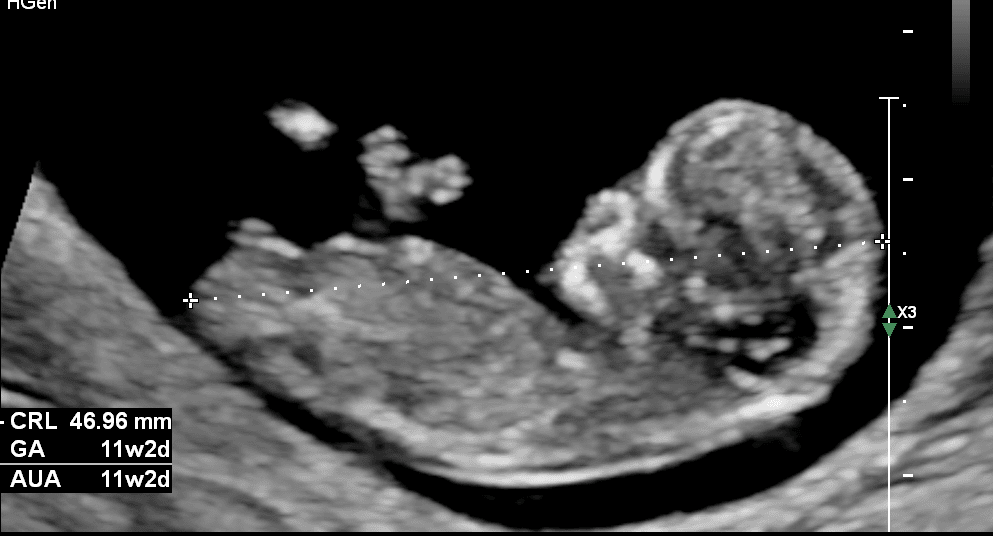

Tijdens deze echo wordt de uitgerekende datum bepaald. Dit is belangrijk te weten, omdat zo een schatting gemaakt kan worden in welke periode de baby geboren zal worden. Ook kan in de zwangerschap de groei van de baby goed vergeleken worden met het aantal weken dat je zwanger bent. De uitgerekende datum staat ook op de zwangerschapsverklaring die je nodig hebt om zwangerschapsverlof aan te vragen. Tijdens de eerste termijnecho wordt soms gezien dat je zwanger bent van 2 of meer kinderen. Om het echo-onderzoek te vergemakkelijken, willen we graag dat je met een volle blaas komt.

De eerste dag van je laatste menstruatie wordt gebruikt om je uitgetelde datum te bepalen, je kunt dan globaal je zwangerschapstermijn berekenen. Wij zullen met een termijnecho de exacte zwangerschapsduur en je uitgerekende datum bepalen. Deze termijnecho kan betrouwbaar gedaan worden tussen 10 en 13+ weken zwangerschap.